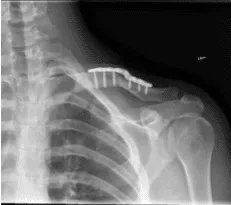

El paciente fue extubado y trasladado a la unidad de recuperación postoperatoria en estado estable. Tras dos semanas, el paciente se registró, con XR presentada y sin lucidez periprotésica. La articulación esternoclavicular muestra alineación normal.

El examen del hombro izquierdo revela que la incisión está cicatrizando bien, sin indicios de drenaje, eritema o calor. Hay pequeñas ampollas en la parte superior y alrededor de la incisión. El rango de movimiento y la fuerza están progresando adecuadamente en esta etapa de la rehabilitación.

Resultados de la radiografía de 12 semanas de la clavícula izquierda tras la cirugía